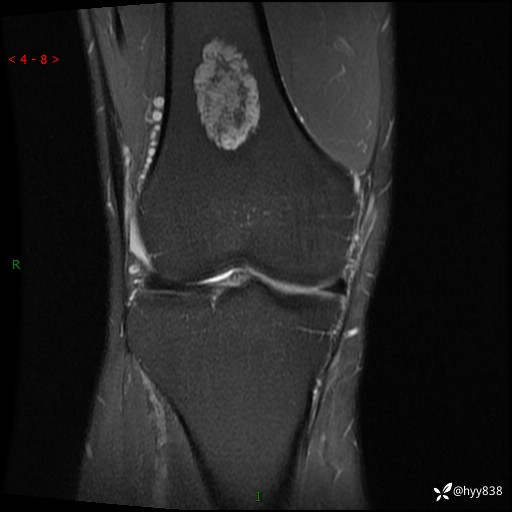

MRI

img